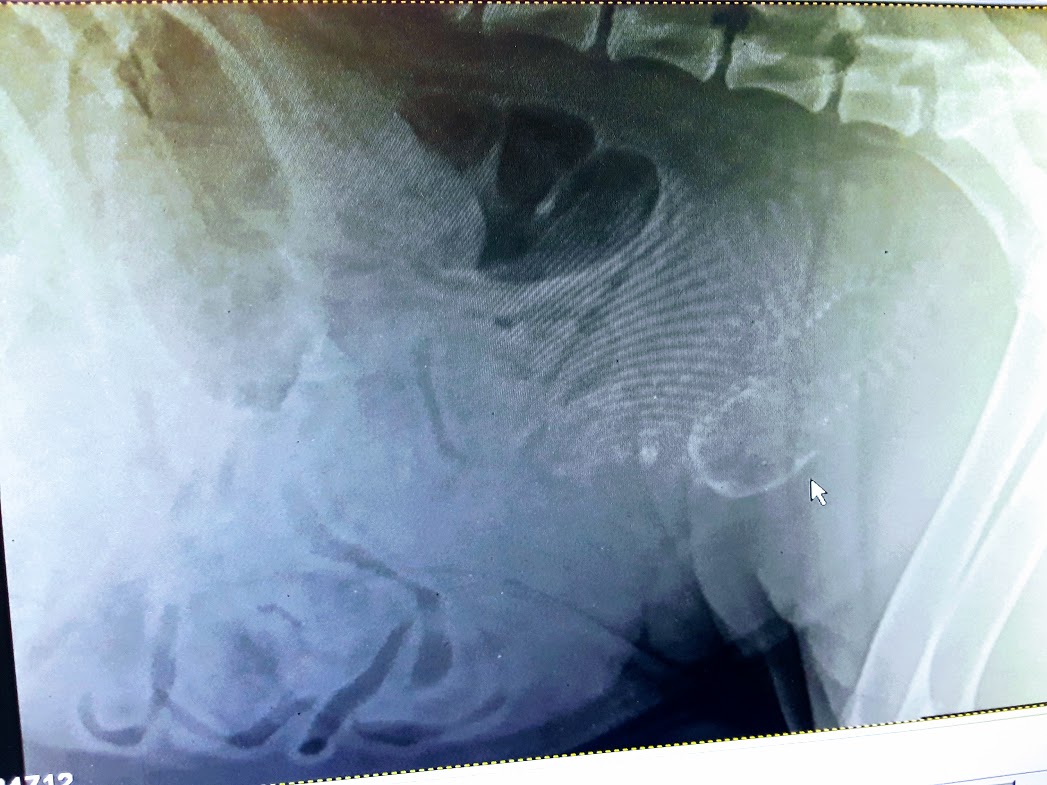

Jose Feneque, DVM (46)

Veterinarian